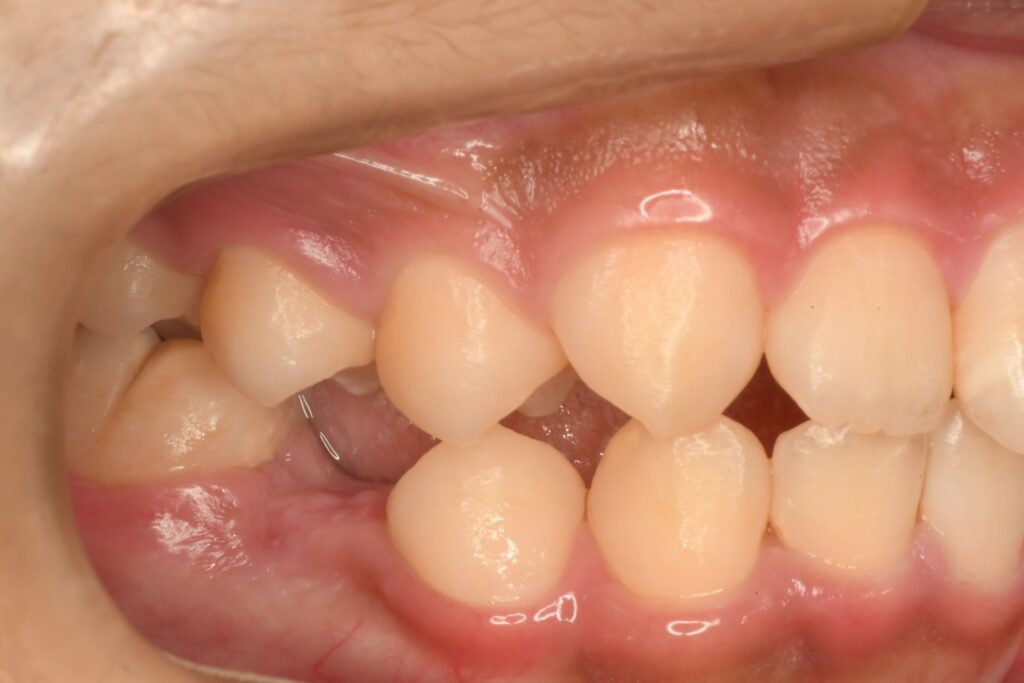

正面から観るとわかりずらいと思いますが、噛み合わせが微妙にズレています。ズレている理由は、歯が1本もともと無いからです。いわゆる先天欠損です。以前から把握できていましたが、色々と相談をしながらどうしようかを考えていました。最初は子供はをできる限り使っていこう‼︎という計画でいましたが、あまり持ちませんでした。歯がなくなっても本人がそれほど気になっていなかったこともあり、歯が無い状態で過ごしつつ、歯の病気にさせないように関わり続けていました。歯を削ったり、インプラントにしたりするのは、できる限りおすすめしたくなかったので矯正治療の提案をしていました。

今回の計画は、数段階に分けて治療をしていきます。1段階目は歯の位置関係をできるだけ整える。2段階目は先天欠損している部位の隙間をなくす。3段階目は全体的にはの位置を整える。ことにしました。結構時間がかかると思いますが、本人もお母さんも同意してくれたので治療を開始することになりました。